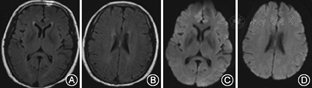

例1、例3均未给予特殊治疗;例1给予80 mg/d甲泼尼龙冲击治疗1周;例4给予抗感染、改善肾功能、纠正贫血治疗;患者临床症状均在1~2周内明显改善。分别于发病后32、7、5、8 d后复查头颅MRI,例1、2、4病灶完全消失(图3,图4)。例3胼胝体压部病变范围减小且异常信号强度减弱。

MRI显示胼胝体压部的孤立性异常信号和病灶的可逆性消失是本病主要的诊断依据。Takanashi等[7,8]根据MRI特点将MRES其分为Ⅰ型和Ⅱ型,即病灶局限于胼胝体压部的Ⅰ型和同时累及深部白质或皮质下白质的Ⅱ。本组3例患者MRI表现为胼胝体压部的孤立的类圆形病变,符合MRES分型Ⅰ型;1例表现为整个胼胝体压部受累的弧形病变,类似于"回旋镖征"[9],同时累及胼胝体外,符合Ⅱ型。Takanashi等[7]发现MRES Ⅱ型可向Ⅰ型转变,胼胝体外的异常信号可先于胼胝体压部的异常信号消失。本组1例患者MRI上DWI仅见胼胝体压部异常信号,而T2WI、FLAIR显示胼胝体及胼胝体外异常信号,推测这种不匹配的其可能的原因是患者行MRI检查是处于Ⅱ型向Ⅰ型转换的中间阶段,胼胝体外病变正逐渐消失,DWI较T2WI及FLAIR能够更敏感的显示这种改变。本研究Ⅰ型和Ⅱ型患者的临床症状及预后方面无差异,与Takanashi等[8]的报道一致。也有研究发现,胼胝体外病变的出现可能提示预后不良[10]。本组4例患者MRI病变在首次行MRI检查后4~17 d消失,患者临床症状的完全恢复晚于MRI病灶的消失。